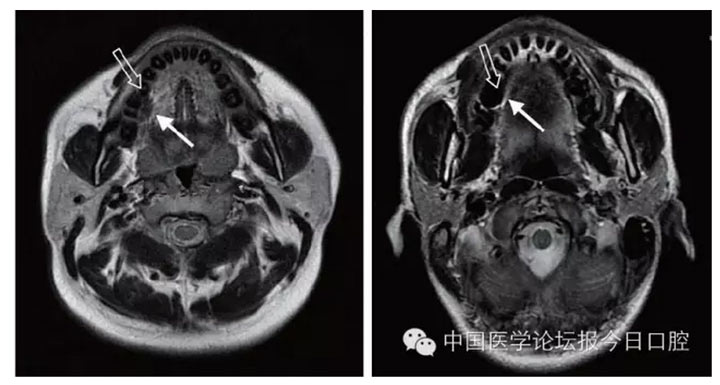

在MRI 檢查中,金屬產(chǎn)生偽影的大小與金屬材料的磁化率及磁場強(qiáng)度相關(guān),磁化率越大、磁場強(qiáng)度越高,產(chǎn)生的偽影越大。偽影不僅使金屬所在處局部解剖結(jié)構(gòu)變形或消失,還會(huì)沿頻率編碼方向擴(kuò)散到遠(yuǎn)處,嚴(yán)重影響被檢查部位及鄰近組織觀察

文獻(xiàn)研究中常使用的金屬包括鎳鉻合金、鈷鉻合金、低鈦合金、純鈦、金合金、金鈀合金、銀鈀合金等成分如表所示。大量研究得出近乎一致性的結(jié)論。金合金、金鈀合金、銀鈀合金對MRI影響甚微,與全瓷材料、丙烯酸樹脂極為相似,表現(xiàn)為修復(fù)體影像邊緣光滑、無變形、無偽影;純鈦金屬對MRI影響較小,接近于全瓷材料;但有的研究卻發(fā)現(xiàn)純鈦在核磁共振場中也產(chǎn)生偽影,但偽影涉及的掃描層數(shù)較少;低鈦合金(鈦合金)對MRI影響較大,介于純鈦和鎳鉻合金之間,中度偽影;鎳鉻合金、鈷鉻合金對MRI影響很大,鈷鉻合金更甚;表現(xiàn)為重度偽影、圖像扭曲變形(圖1、圖2)。不難看出,對MRI 影響,全瓷材料、樹脂材料<金合金等貴金屬<純鈦<低鈦合金<鎳鉻合金<鈷鉻合金。有研究發(fā)現(xiàn)鈷鉻合金橋偽影大小與修復(fù)體長軸一致,影響范圍為固定橋近遠(yuǎn)中徑2倍,頰舌徑的4倍;相同外形金屬修復(fù)體厚度增加,偽影增加。單個(gè)金屬樁核偽影可波及到上頜竇、牙槽骨、舌體、舌下腺等組織器官,但對眼底、眼內(nèi)容物、腦組織和頸椎成像基本無影響。